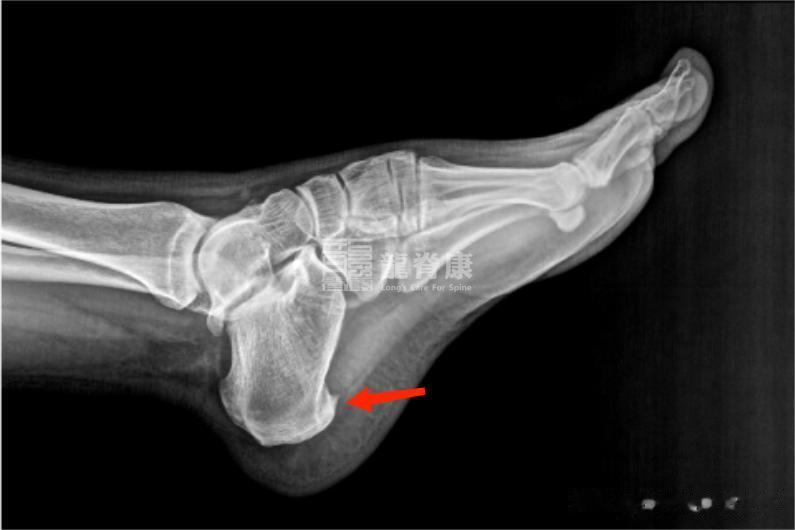

骨刺常被认为是尖锐的东西扎在肉里,其实它本身不直接引起疼痛。骨刺是身体的一种代偿反应,当足底筋膜在跟骨附着点被过度牵拉时,身体会自我修复,时间长了可能钙化形成骨刺。通常是在足底筋膜炎的基础上出现的。

症状和足底筋膜炎非常相似,也是脚跟底部痛。但骨刺患者的疼痛点可能更固定,按压时有明显的尖锐感。通过X光片可以明确看到跟骨前方有骨性突起。

很多人看到X光片上的骨刺就认为是它导致疼痛,其实疼痛主要还是来自筋膜的炎症。治疗的重点也是消除炎症和改善力学环境,而不是切除骨刺,除非骨刺非常大或保守治疗无效。